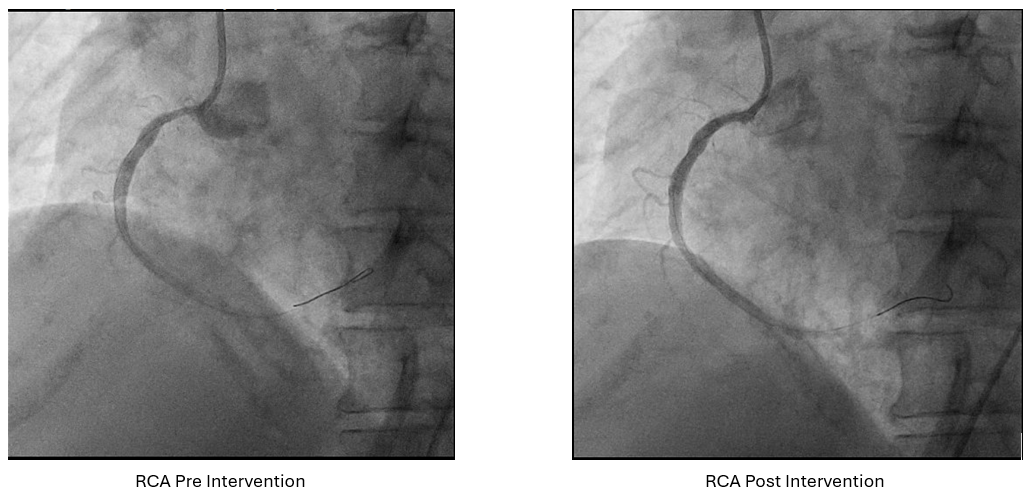

Dominant RCA with osteo-proximal tubular 70% stenosis; Normal LM; Diffuse LAD stenosis from ostial to distal with 90% stenosis at proximal; and tubular osteo-proximal 80% stenosis on LCx.

Angiography : LCA and RCA cannulation was confirmed by saline injection with ECG changes monitoring. 2 cc of contrast was pushed by 8 cc of saline for each view, with as minimal but optimal views as possible. Angiography roadmap was recorded. PCI LCA: Two workhorse wires was advanced to distal LAD and LCx using roadmap guidance. IVUS was inserted to evaluate morphology and length of LAD and LCx lesion as well as vessel size. The LAD IVUS results showed osteal-proximal fibrocalcified 90-180¡Æ with MLA of 1.66 mm2, while LCx IVUS also showed osteal-proximal fibrocalcified 180-270¡Æwith MLA of 3.07 mm2. Osteal-proximal LAD and LCX was then predilated with scoring balloon of 3.0x15 mm and 2.5x15 mm respectively, using guidewires as geometry guidance. IVUS evaluation suggested calcium crack, plaque dissection and lumen optimization. DCB 3.5x40 mm was then deployed at LM-LAD and DCB 3.0x40 mm at LM-LCx. One more view of low contrast angiography showed optimization of proximal LAD and LCx. IVUS evaluation showed MLA improvement from 1.66 to 6.17 mm2 (LAD) and 3.07 to 4.96 mm2(LCx). PCI RCA : Same approach was performed to RCA osteo-proximal lesion, predilatation using scoring balloon 4.0x12 mm followed by DCB 4.0x20 mm implantation, resulting with improvement in both angiography and IVUS evaluation (MLA improved from 5.36 to 7.11 mm2). Throughout of the procedure, only 18 cc of contrast were used.

Case Summary